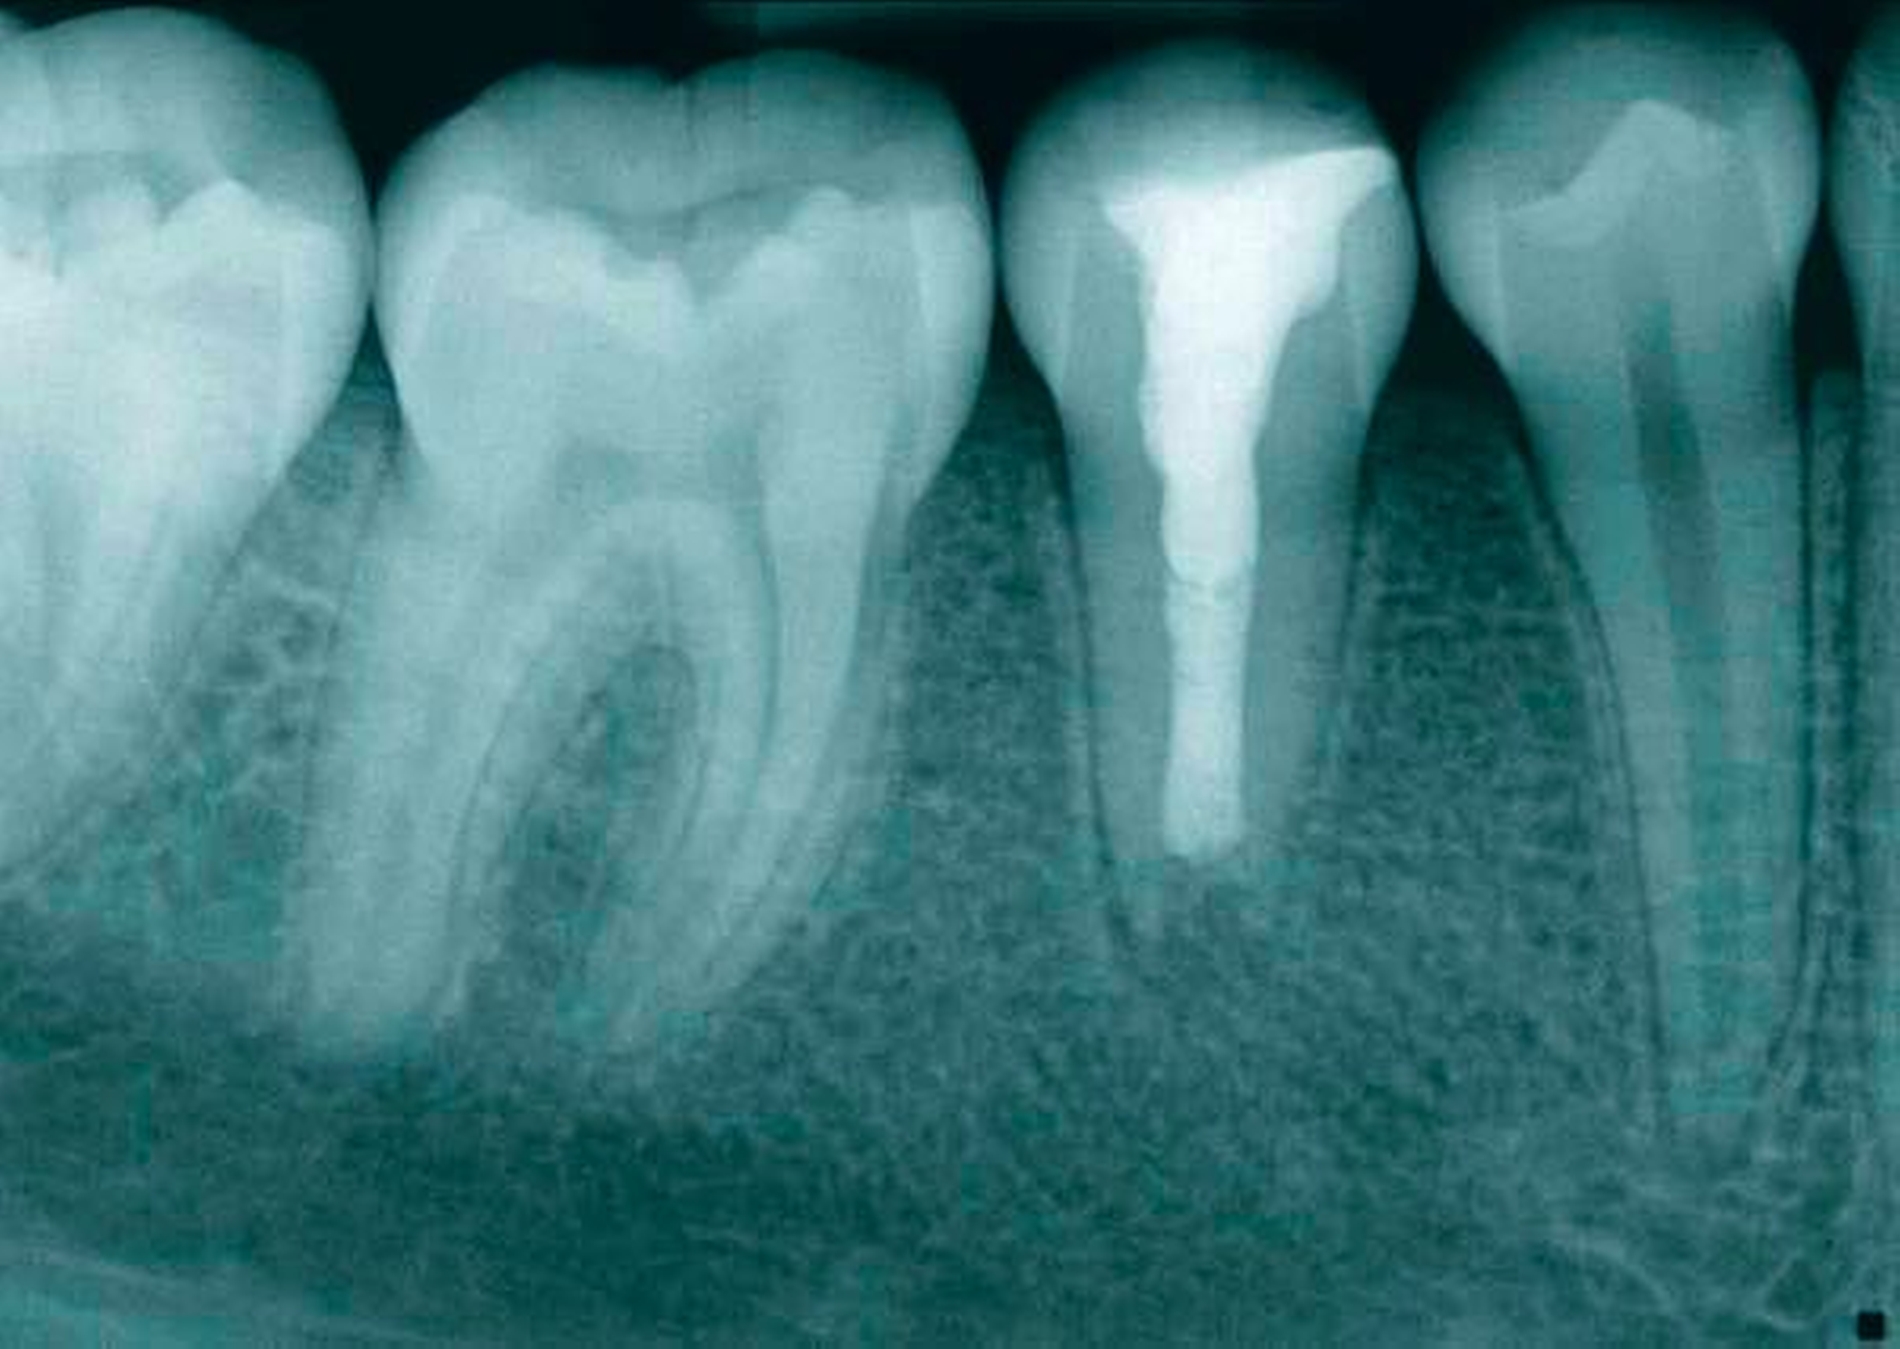

Das Ausgangsröntgenbild (Abbildung 1) der Regio 44–46 zeigte eine apikale Transluzenz im Bereich der Wurzelspitze des Zahnes 45. Der Zahn weist ein nicht abgeschlossenes Wurzelwachstum mit weit offenem Foramen und weitlumigem Wurzelkanal auf. Im Bereich der klinischen Zahnkrone imponiert eine transluzente, kariesdichte Zone, die sich vom mesialen Anteil der Krone bis ins Pulpenkavum erstreckt. Die Fissur des Zahnes scheint stark invaginiert und ist radiologisch nachzuvollziehen.